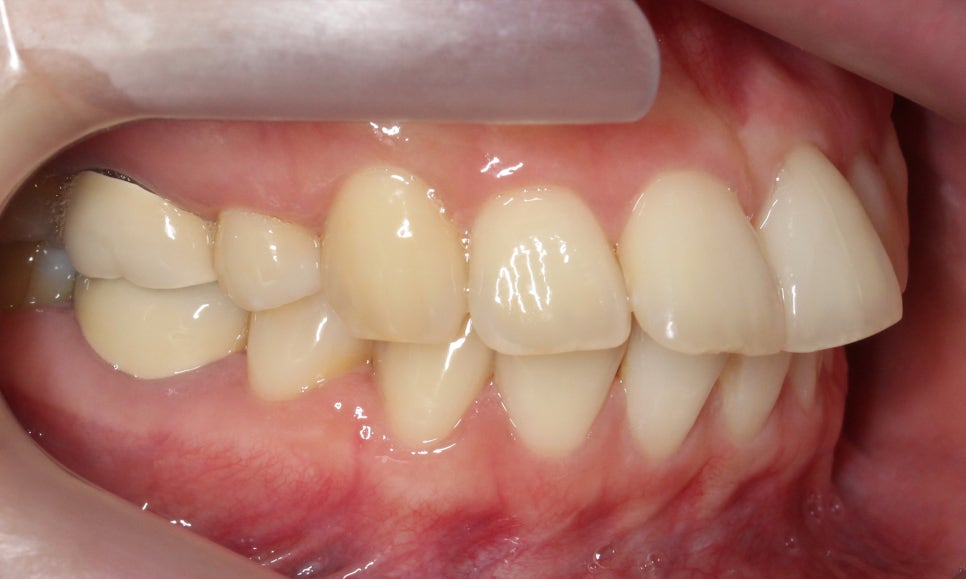

측면에서 치아의 돌출감을 살펴보면

상악 교정 후 중절치가 튀어나온 증상이

크게 완화된 모습인데요,

비발치 교정이기 때문에

완전하게 돌출감이 사라지지는 않았지만

스마일라인이 어색하지 않도록

자연스럽게 돌출감을 교정한 모습입니다.

좌우 교합 평면 사진에서도

클리피씨교정을 끝내 상악이

하악에 비해 비교적 가지런하게

배열된 모습으로

중절치의 각도가 특히

바르게 바뀐 모습입니다.